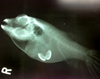

For the past 8 years, Veterinary Practice News has had an annual x-ray contest for the craziest things pet's have eaten. Here are the winners for 2013.